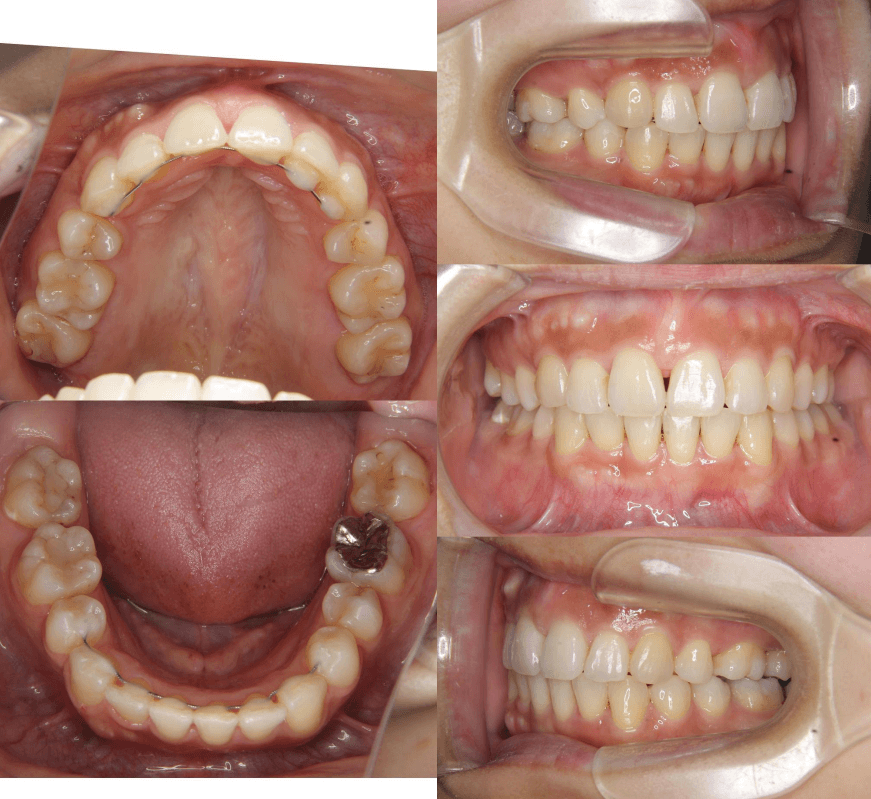

| 年齢・性別 | 25歳女性 |

|---|---|

| 主訴 | 前歯の歯並びの乱れ(叢生)を気にされて来院された。咬み合わせや審美的な改善を希望されていました。 |

| 治療期間・回数 | 4年5ヶ月・30回 |

| 費用 | 1100,000円(税別) |